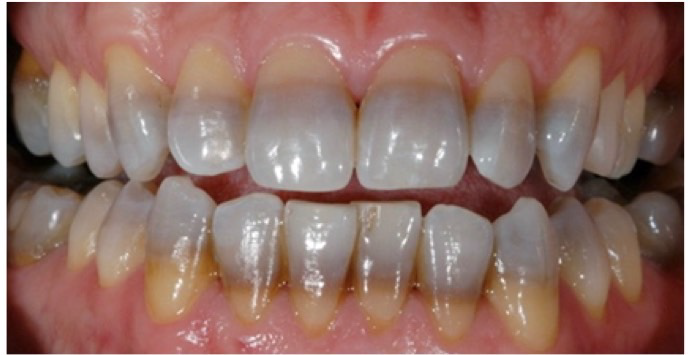

Tetracyclin Stain (TC stain)